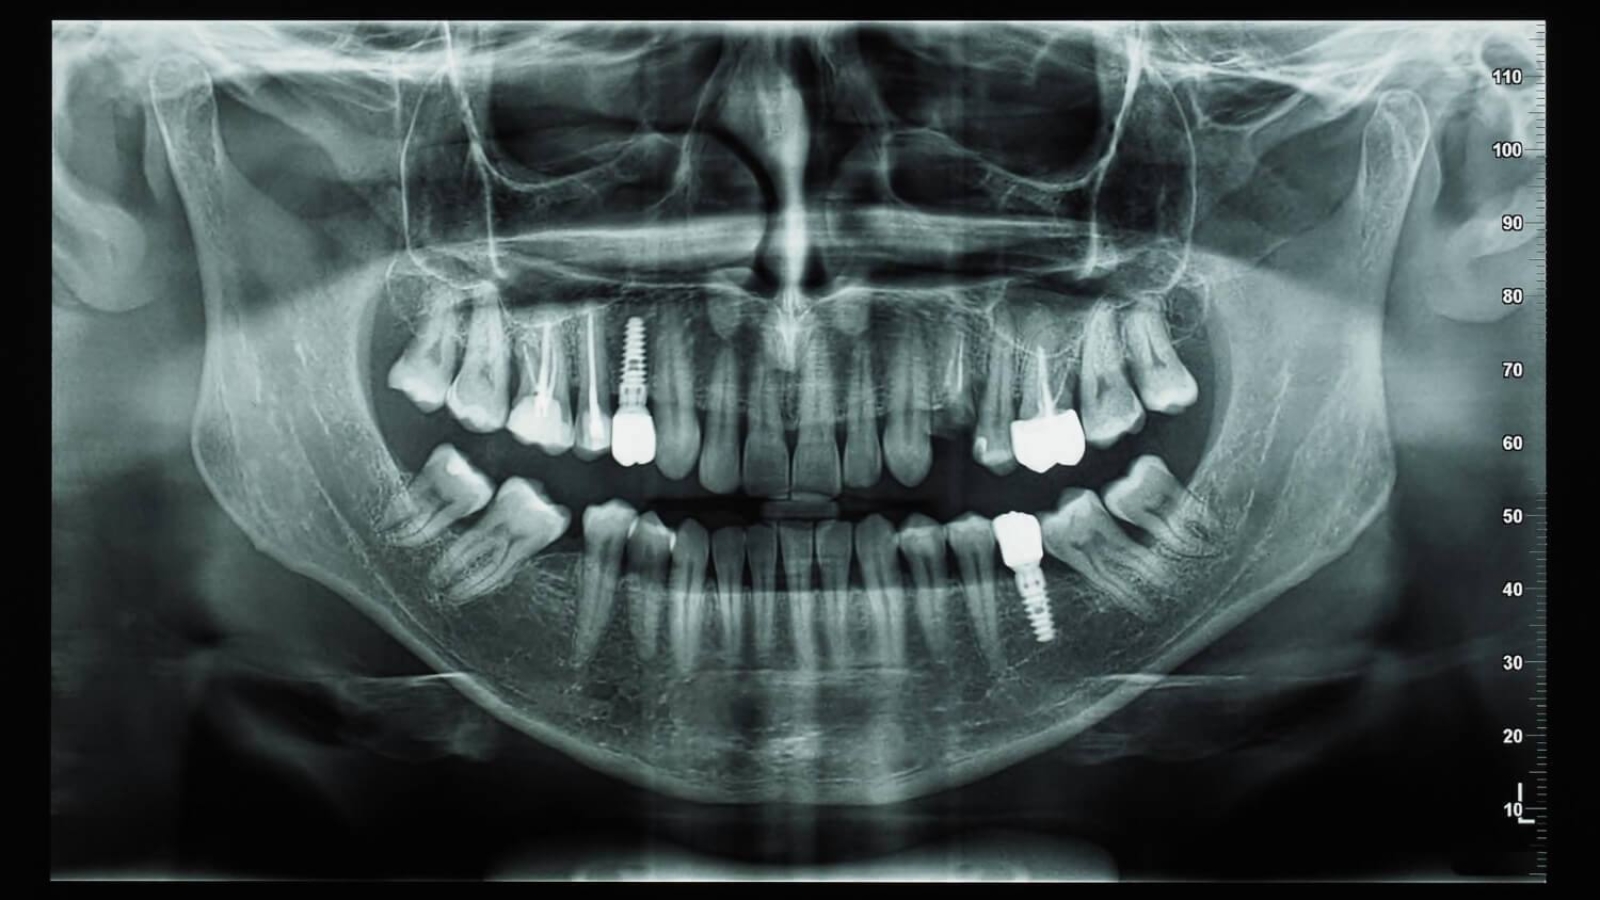

An orthopantomogram is a panoramic dental X-ray that provides a comprehensive image of both jaws, the teeth, and surrounding bone structures. This diagnostic method is widely used in modern dentistry because it allows dentists to evaluate the entire dental system in a single image. Professor Alexander von Breuer says that panoramic imaging helps clinicians understand the overall functional relationships within the oral cavity and detect structural changes that may not be visible during a routine examination. In the clinical approach used at DentalClinic24, orthopantomography is considered an essential step in obtaining a detailed overview of the patient’s oral condition.

One of the key advantages of an orthopantomogram is the amount of information it provides. Unlike localized X-rays that focus on a small section of the dental arch, panoramic imaging captures both jaws at once. This allows dentists to analyze tooth alignment, root morphology, bone structure, and even the presence of developing teeth that have not yet erupted. Such a broad diagnostic perspective helps specialists evaluate the overall situation before planning treatment.

This diagnostic technique is particularly important when preparing for dental implant placement. Before implants are inserted, the dentist must carefully assess the volume and density of the bone tissue, as well as the location of adjacent teeth and anatomical structures. A panoramic X-ray provides essential information that helps doctors develop a safe and well-planned treatment strategy. In clinical practice at DentalClinic24, orthopantomograms are frequently used as part of the preparatory evaluation before implant procedures.

In oral surgery, panoramic imaging assists dentists in planning complex procedures. For example, before removing impacted or difficult teeth, the dentist can analyze the shape and orientation of the roots and their proximity to important anatomical structures. Such evaluation improves surgical precision and helps reduce the risk of complications.